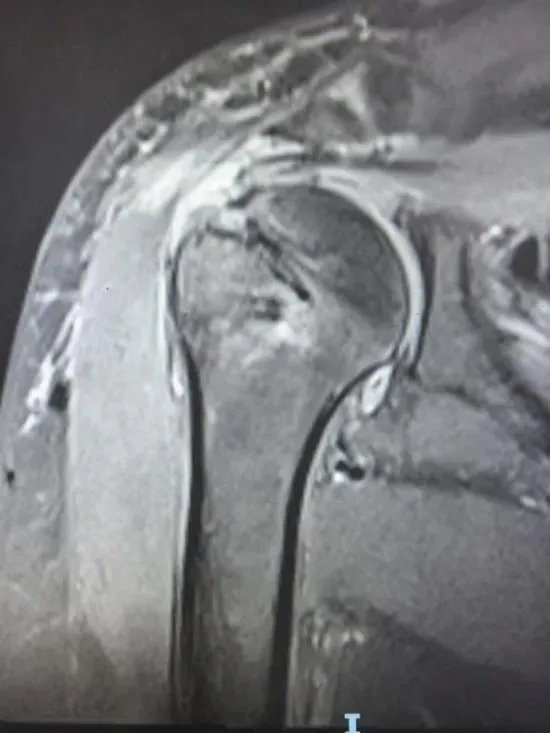

术后所见如上图

针对这些难题,团队反复讨论,最终制定了“个体化翻修手术+PRP协同治疗”的方案,最终与患者及家属沟通并征得同意,从解剖重建、功能修复到生物学优化层层突破技术瓶颈。整个手术耗时147分钟,术后即刻被动前屈、外展活动度已恢复至150°!

出院前复查,患者的疼痛评分从术前的8分(剧痛)降到了2分(轻微不适),被动前屈能到140°、外展125°,基本能满足日常活动需求。